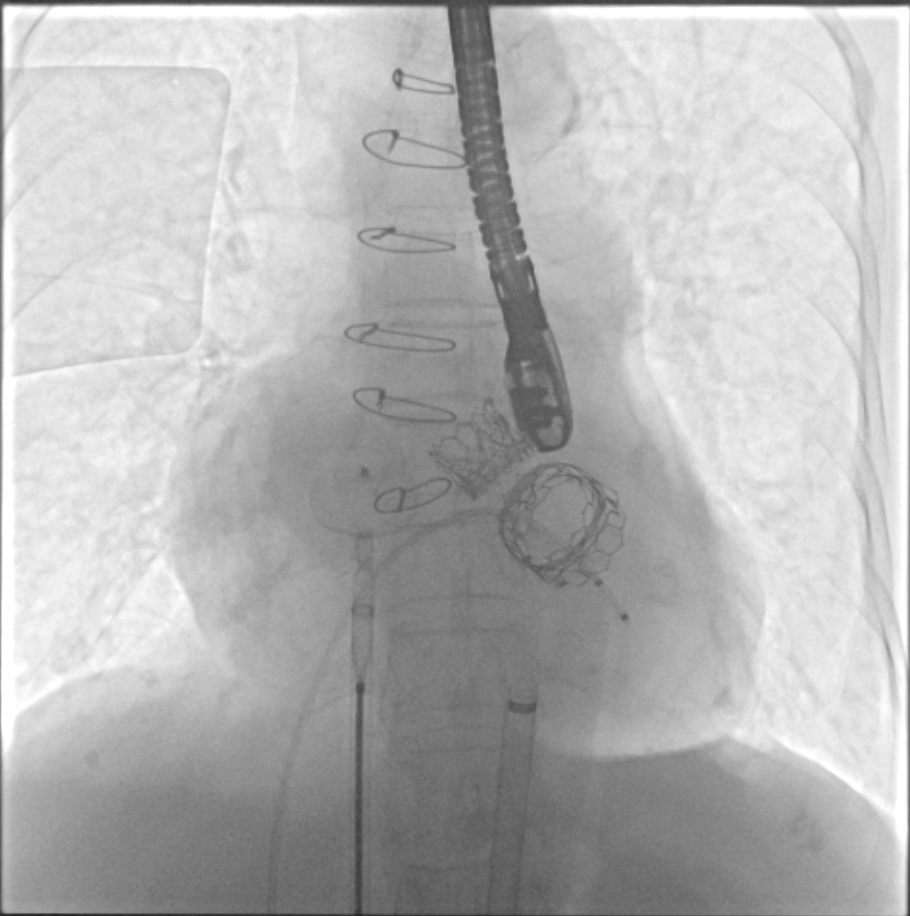

术前(图1)和TAVR 植入(图2)

TMVR 术后房间隔封堵

在经过术前CTA评估测量等检查后,正式手术在珠海市人民医院医疗集团的百级层流复合手术室内进行,在林阿姨全麻的情况下使用食道超声及X线监测指引,经过3小时的紧张手术,双瓣中瓣手术最终成功完成。